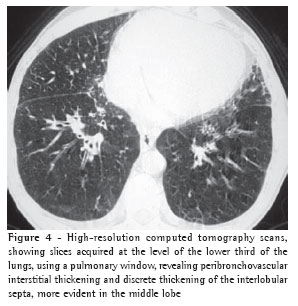

Overall, ground-glass opacities and thickening of the interlobular septa were the most common findings, occurring in 100% of the cases (Figures 1 and 2).

The thickening of the interlobular septa was bilateral in thirteen cases (Figures 1-4) and unilateral in two, also in the patients with fibrosing mediastinitis. In all cases, the thickening was of the smooth type.

All cases of interlobular septal thickening (100%) were accompanied by ground-glass opacities. Nevertheless, the mosaic pattern of attenuation was observed in only ten cases (66%) (Figure 1).

Pleural effusion was the third most common tomographic finding overall and was the most common nonparenchymal finding, being found in 13 patients (87%), predominantly in the bilateral form (n = 11) (Figures 1-3).